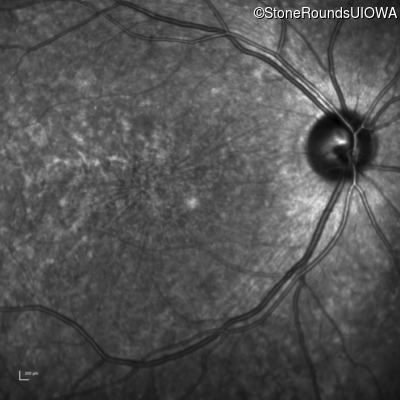

AR Stargardt Disease (IIA)

Age at visit: 32 years

This 32 year old man first noticed difficulty reading road signs when he was 21 years old.

AR Stargardt Disease ABCA4 Arg681Stop CGA>TGA Arg1860Trp CGG>TGG AR